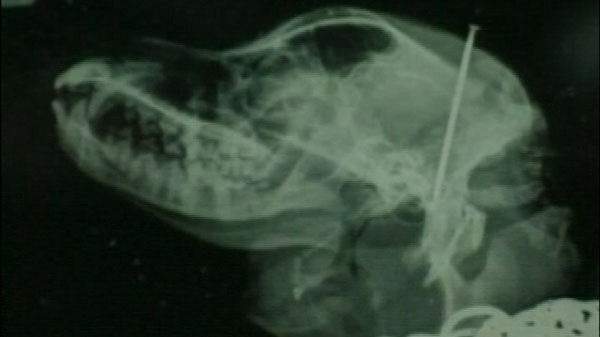

Photo CTV | An X-ray showing the mother dog with a nail in her skull is seen in this undated photo.

Animal protection services took all the dogs to the vet. The mother, who also had a long nail lodged in her brain, was treated there and is recovering.